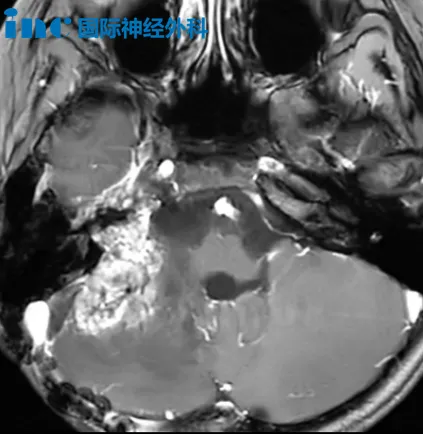

33岁林女士因意外摔倒检查发现左侧桥小脑角区(CPA区)存在36×32mm占位病变。鉴于手术高风险,患者首选射波刀放疗,但治疗后肿瘤未显著缩小,反而出现面部抽搐、眼周跳动伴耳鸣头晕等症状。

巴教授术前评估指出:"尽管既往放疗可能增加神经粘连风险,但我们具备处理此类情况的专业方案。"他形象地比喻手术策略:"肿瘤如同杯体,周围神经好似缠绕的线缆,需要精细分离保护。"最终在苏州大学附属第四医院成功完成肿瘤切除手术。